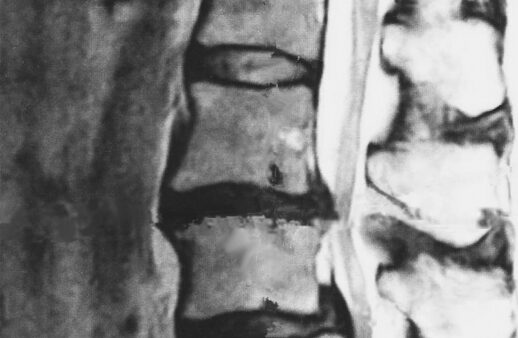

MRI検査で、「ヘルニアがあるから腰痛なんだ」これも先述のとおり間違いです。ヘルニアが出ていても症状がない方もいます。画像検査でヘルニアの有無を確認し、徒手検査でヘルニアによる神経症状が一致して初めてヘルニアの診断となります。

※無症状のヘルニアは60歳未満では20%、60歳以上では40%の方が持っているという研究結果もあります。